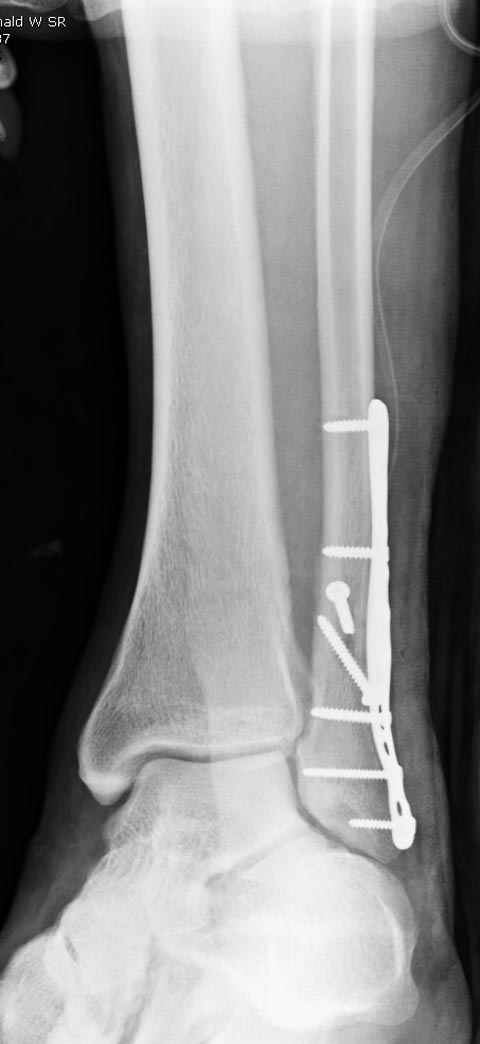

Уважаемые коллеги! Как и обещал, представляю плоды своей работы. Хвалиться особо нечем. Пошли задним

доступом сначала к м/берцовой кости, благодаря смещению линию перелома удалось сразу дифференцировать и по ней узким долотом (без молотка) мобилизовали отломки. Затем выделили задний край, там было проще пройти по линии перелома. Далее пластина по задней поверхности в дистальный отломок, винт проксимальнее пластины и дистрактором с трудом растянули отломки, ощущение было идеальной репозиции м/берцовой кости( доступен осмотр по задней и наружной поверхности), далее винты стандартно. Кстати, положение больной на боку: очень неудобно, но по-другому потом не повернуть на спину, чтобы сделать снимки в стандартных проекциях (ЭОПа нет). Затем дистрактор (два полукольца, спицы), репозиция заднего края, спонгиозный винт с шайбой, слишком проксимально, поэтому + еще один. Доступ к дельтовидной связке: рубец в передней порции, частично иссечен, шов. В общем, длительность операции 3,5 часа, а сказать, что все задуманное получилось, не могу.

Отправитель: Djpldas Kuldjanov 16 Март 2006, 17:11

Отличная, грамотная работа, поздравляю, я бы держал в гипсовой повязке до трех недель, затем разработку сустава без нагрузки, нагрузку при такой фиксации,

думаю, можно начать в 6 недель.

Все таки нужно было стянуть ДМС. Судя по снимкам остался подвывих.